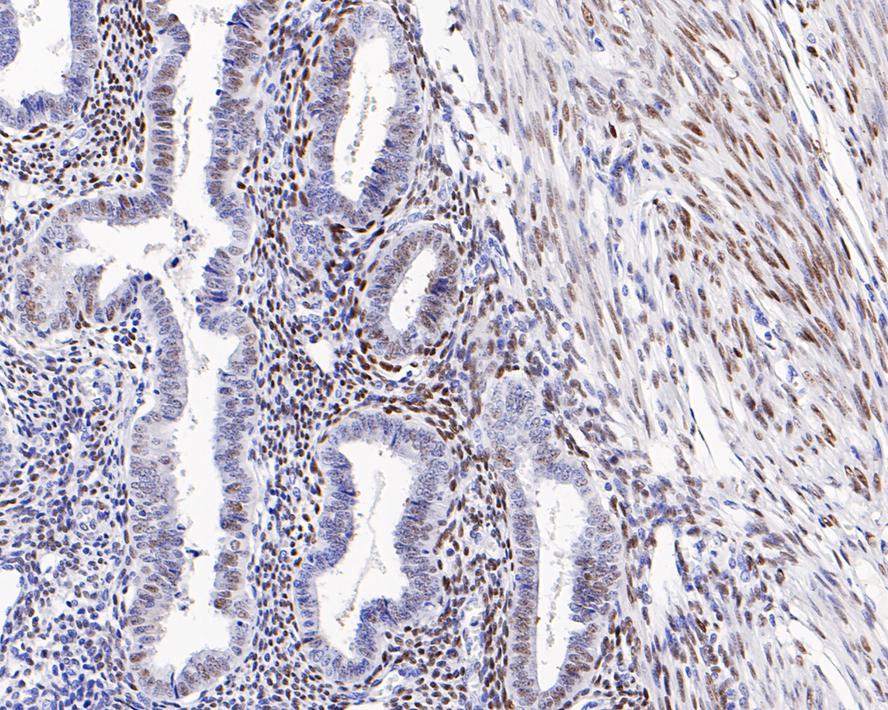

Catalog# HA721140

Estrogen Receptor alpha Recombinant Rabbit Monoclonal Antibody [PD00-04]

Application

IHC-P

Reactivity

Human